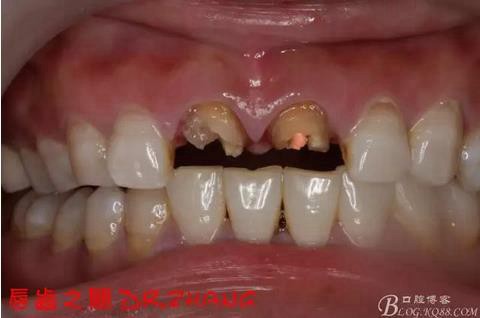

主訴:左上門牙腫脹數(shù)日

現(xiàn)病史:患者自訴兩年前在外院做了門牙的修復(fù) 一個月前左上門牙腫 服藥后消腫 前幾日腫脹厲害 影響正常生活 現(xiàn)來我院 要求治療

檢查:11 21金屬烤瓷冠 21根尖部牙齦紅腫 牙痛 叩(+++)冷刺激無反應(yīng) 11無不適癥狀 全口牙周情況良好